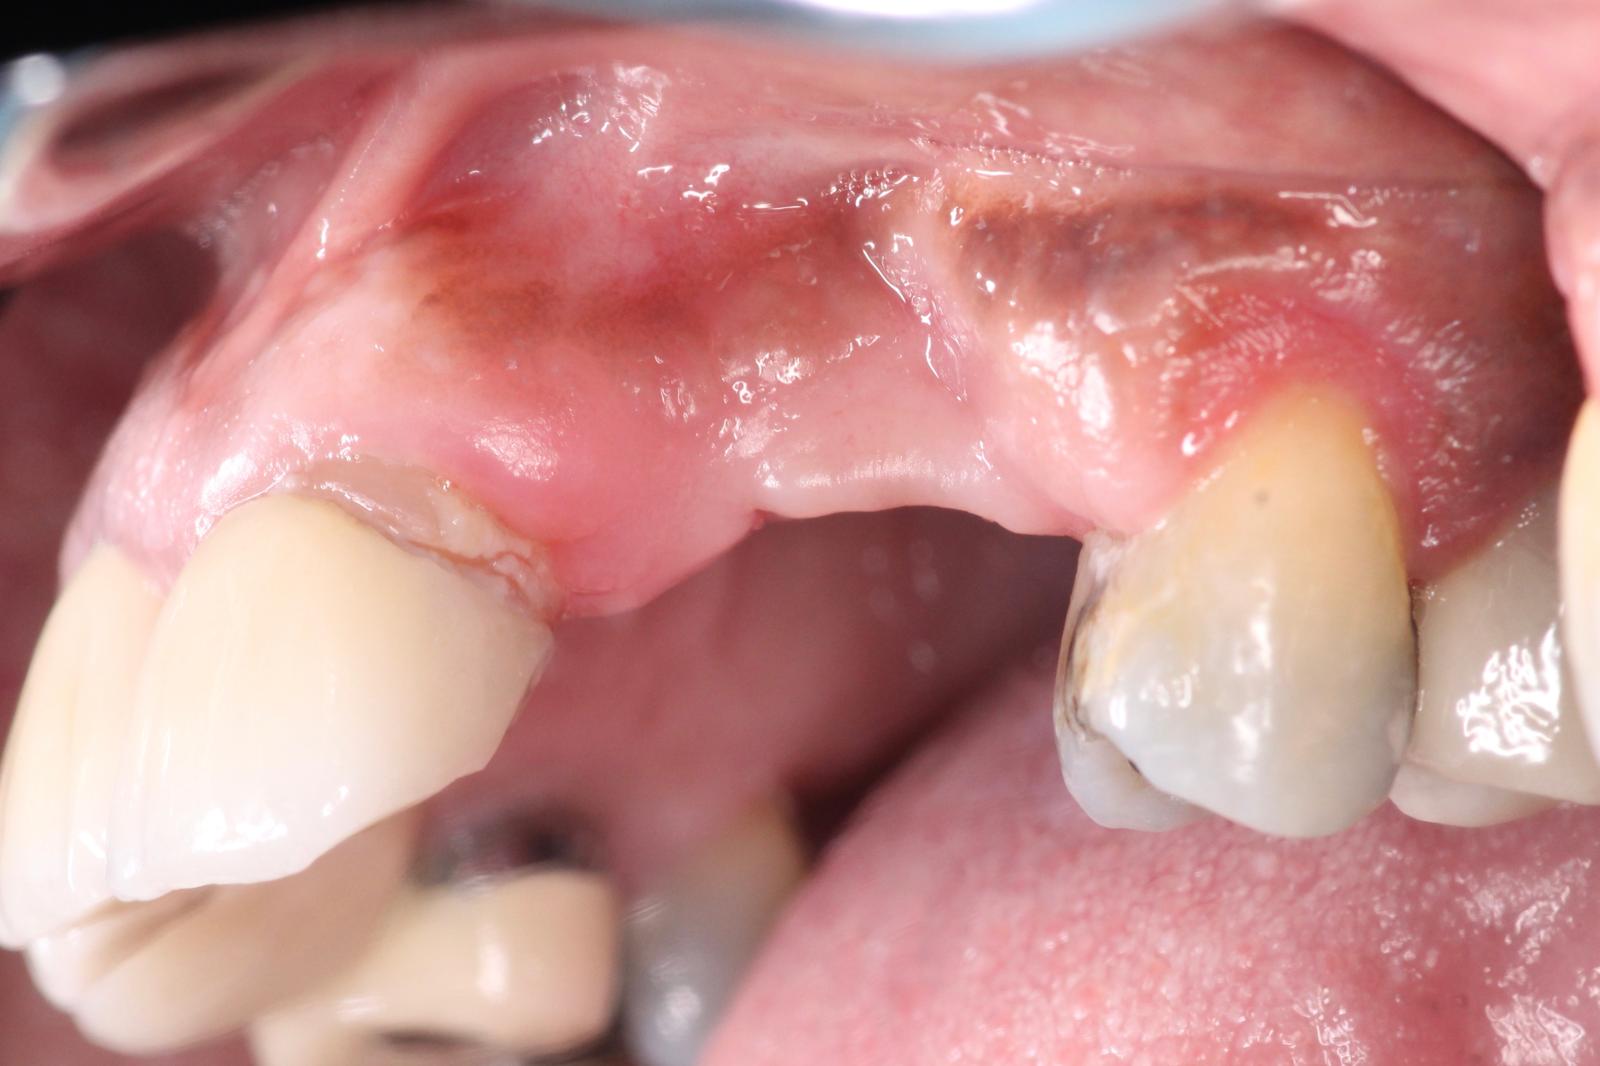

Missing 10 & 11 were extracted a year ago. Implants were placed, but healed terribly. The failed implants were removed, and now the site presents with significant bone loss, and severe resorption.